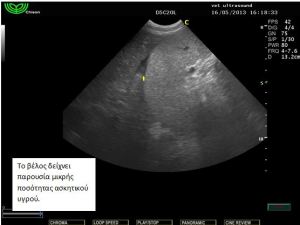

Ευρήματα: Στον υπέρηχο εντοπίστηκε μικρή παρουσία ασκητικού υγρού και μία μάζα στρογγυλή σαφώς περιγεγραμμένη χωρίς να δείχνει να έχει πρόσφυση σε κάποιο όργανο. Το τοίχωμά της φαινόταν αρκετά παχύ και στο εσωτερικό υπήρχε παρουσία παχύρρευστου υγρού. Στη διαφορική διάγνωση υπήρχε η υποψία για κάποιο απόστημα της περιτοναικής κοιλότητας, κύστη του μεσεντερίου και η δίλοβος εντερική κύστη (intestinal duplicated cyst). Μετά από χειρουργική εξαίρεση βρέθηκε πως η κύστη αυτή ήταν κολλημένη πάνω στο παχύ έντερο από την μία πλευρά και από το μεσεντέριο από την άλλη. Το περιεχόμενο ήταν μία άμορφη ουσία παχύρρευστη. Το τοίχωμα της κύστης έμοιαζε με το τοίχωμα του εντέρου. Η διάγνωση τέθηκε τελικά ως δίλοβος εντερική κύστη.